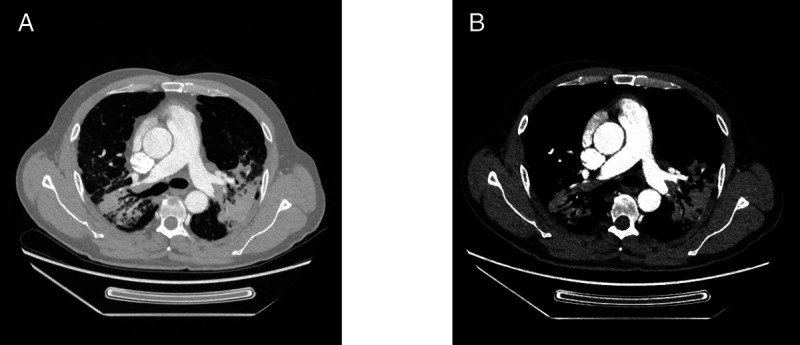

Endobronchial ultrasound-guided transbronchial tunnel Cryobiopsy for mediastinal lymphadenopathy (with video).

超声引导下经支气管隧道低温活检治疗纵隔淋巴结病(附视频)。